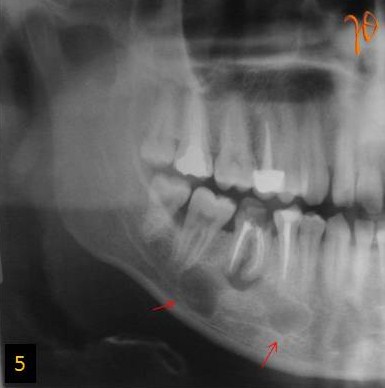

5

Εικ. 5: Στην πανοραμική ακτινογραφία απεικονίζεται πολύχωρη διαύγαση στο δεξιό σώμα της κάτω γνάθου (βέλη).